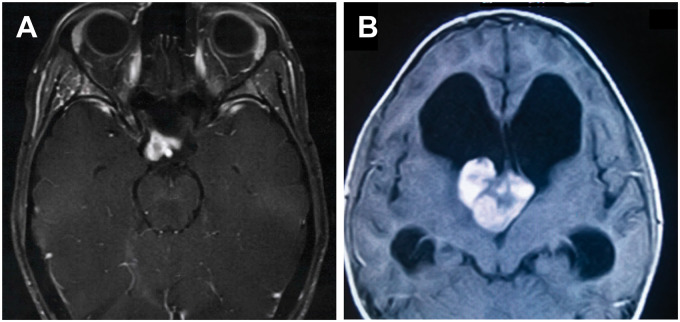

间脑神经胶质瘤的放射学特征。(A) T1加权磁共振成像(MRI)显示视交叉和右侧视神经受累,可见一对比增强的部分囊性肿块。(B) T1加权MRI显示第三脑室前部可见一巨大、分叶状、对比增强明显的肿块。注意侧脑室明显梗阻性脑积水。